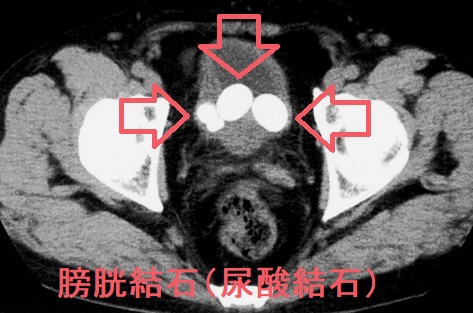

膀胱結石は成分別に

- 尿酸結石;赤レンガ色の結石。甲状腺機能亢進症/バセドウ病、甲状腺機能低下症/橋本病で高尿酸血症(高尿酸血症と甲状腺)

膀胱結石の検査所見は

- 腹部超音波(エコー);結石が写る

- X線;結石が写る

- CT画像;結石が写る

膀胱異物(バルーンカテーテルの断片)、膀胱腫瘍が石灰化して膀胱結石のように見える事があります。